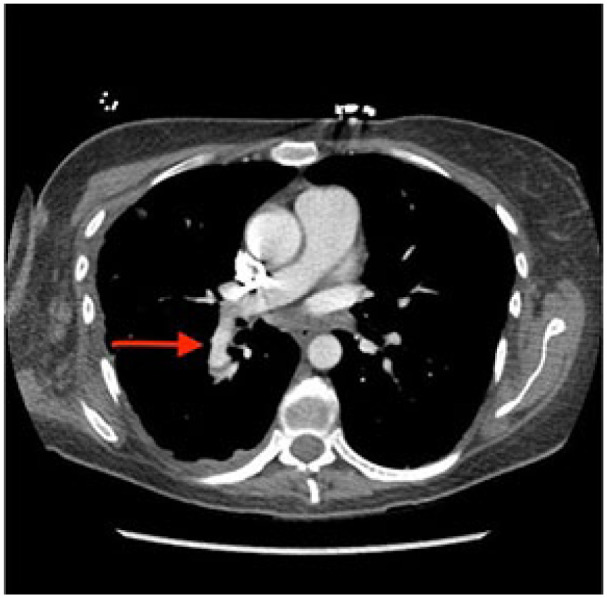

Pulmonary artery pseudoaneurysms (PAPAs) are rare and potentially fatal vascular complications that often require early detection. Most common etiologies are infection and trauma (including iatrogenic from procedures like pulmonary artery catheterization or lung biopsy). Early clinical signs include hemoptysis, dyspnea, and hemodynamic instability. Diagnostic workup should always include appropriate imaging modality, with computerized tomography (CT) and CT angiography as important diagnostic tools. Given the limited number of reported cases, treatment is not definitive and is largely guided by symptoms and patient present. In the case of massive hemoptysis, coil embolization or pulmonary vascular stenting is the preferred option. In the current case of asymptomatic PAPA, we will outline a more conservative approach to treating PAPA.